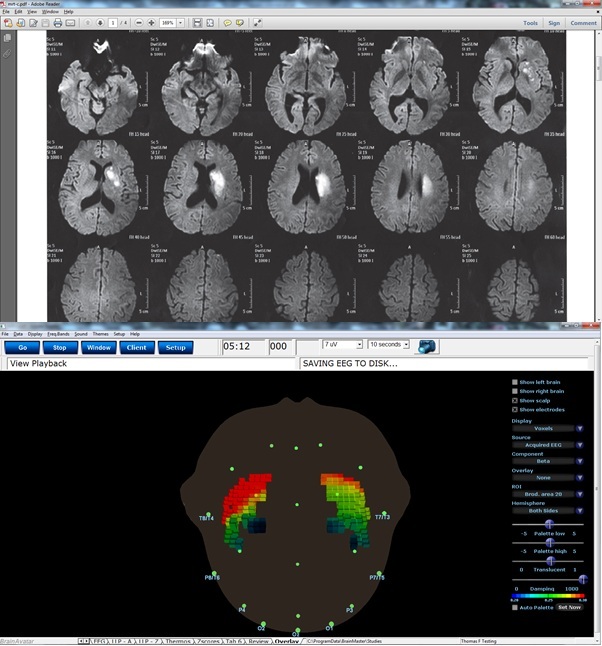

The following example shows an MRI of a client with a brain lesion that is detectable as a degeneration of the right insula. This was also detectable using sLORETA EEG imaging, by comparing the right and left insula in the beta band. As shown, the BrainAvatar sLORETA image also shows the reduced activity on the right side, confirming the MRI result. As an alternative application, this suggests that BrainAvatar sLORETA could be used as a screening, to indicate suggested areas of dysfunction, indicating the need for further study such as the more expensive MRI. This example shows that every voxel in BrainAvatar is converted to a quantity, the current-source density. This provides significant detail in space as well as time, when using this imaging approach. The current-source density data can also be used live for neurofeedback training, using any frequency bands or combination of frequency bands.

We would like to thank Thomas Feiner for providing this example.